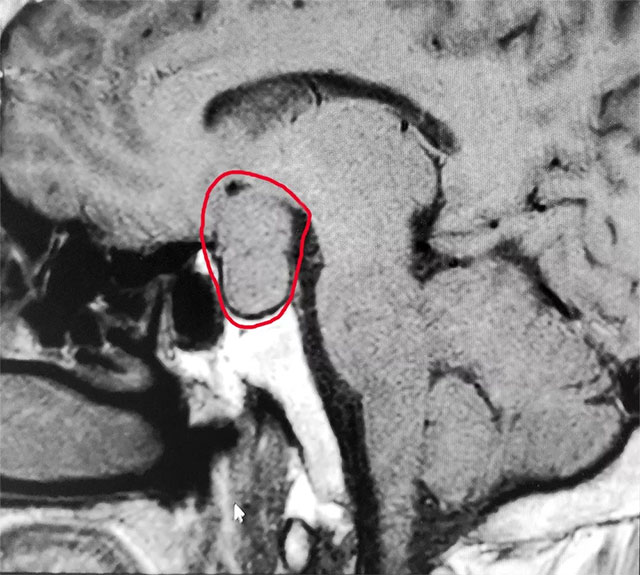

▲ 术前MR影像:垂体大腺瘤,超蝶鞍生长

针对患者情况,6B病区主任潘仁龙基于多年临床经验立即作出判断,急行头颅鞍区MRI平扫+增强,显示:蝶鞍扩大,鞍底骨质下陷;鞍内垂体上缘膨隆,腺垂体中央见一枚类椭圆形异常信号,大小约2.8*1.9cm;T1WI上呈等信号、T2WI呈等信号为主局部见斑片状低信号,轮廓光整,增强后可见大部分明显强化,视交叉可见上抬。考虑为垂体腺瘤伴局部卒中。

潘仁龙主任指出,CT在垂体卒中急性期平扫时即可见瘤内的高密度影出血灶,很容易辨别,但当进入亚急性期后则呈等密度,难于鉴别。因此,在高度怀疑垂体卒中的病例中应首选MRI扫描。此外,MRI 还能提供较 CT 更为清晰的三维空间解剖结构,它对肿瘤以及瘤体与周边正常组织的关系都可起到良好的显示作用。因此MRI是垂体瘤卒中的首选影像学检查手段,而在急性期,尤其是超急性期则首选CT。